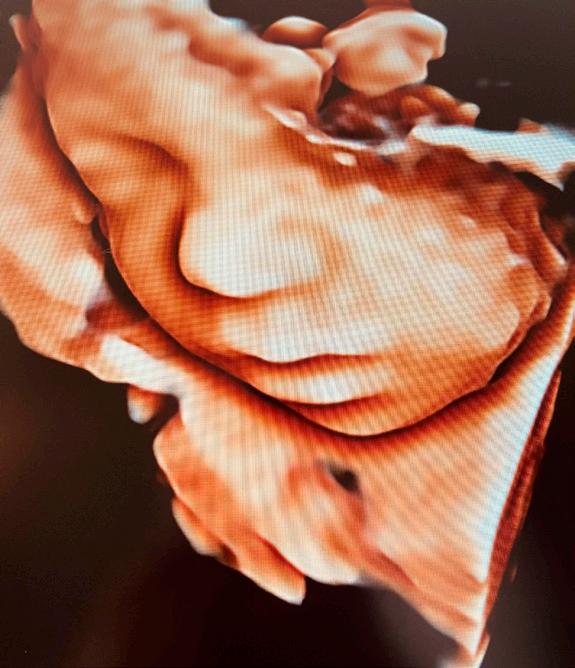

Barnshafandi konum á Suðurnesjum gefst nú í fyrsta sinn tækifæri til að fara í þrívíddarsónar í heimabyggð. Margrét Knútsdóttir, ljósmóðir, hefur látið draum sinn um kaup á sónartæki rætast. „Ég hef endalausan áhuga á öllu sem viðkemur meðgöngu og fæðingu. Ásamt því að sinna ljósmóðurstarfinu til fjölda ára hef ég meðal annars kennt meðgöngujóga í að verða 15 ár og brenn fyrir því að gera meðgöngu kvenna sem ánægjulegasta. Mig hefur því í mörg ár dreymt um að eignast þrívíddarsónar og að geta veitt þessa þjónustu á Suðurnesjum“, segir Margrét ánægð en einnig verður hægt að koma til hennar í svokallaðan kynjasónar eftir 16. viku meðgöngu.

Kíkja á krílið

Meðganga er oft spennandi tími í lífi verðandi foreldra og í sónarskoðun gefst möguleiki á að að kíkja á krílið og tengjast því enn frekar. „Í þrívíddarsónar, sem konur koma í á um sjöunda eða áttunda mánuði meðgöngu, er hægt að sjá krílið hreyfa sig og ef til vill vinka, teygja úr sér eða opna augun. Eitthvað sem getur verið einstök upplifun. Þá get ég einnig útbúið stutt myndband í skoðuninni sem foreldrar fá sent ásamt nokkrum myndum,“ segir Margrét en ítrekar að svona skoðun er ein-

ungis

Notaleg upplifun

Fyrirtæki Margrétar nefnist Lífsins tré og er með aðsetur að Aðalgötu 60, í sama húsnæði og heilsu gæslan Höfða. Hægt er að velja á milli kynjasónar/tvívíddarsónar frá viku sextán og þrívíddarsónar frá viku 26 til 32 á meðgöngu. Skoð unin fer fram í hlýlegu og notalegu umhverfi og mikið lagt upp úr því að gera upplifunina sem besta. Margrét ætlar fyrst um sinn að bjóða upp á tíma síðdegis á virkum dögum en hægt er fá nánari upp lýsingar og panta tíma í gegnum vefsíðuna hennar

til gamans gerð og ekki um fósturgreiningu að ræða.